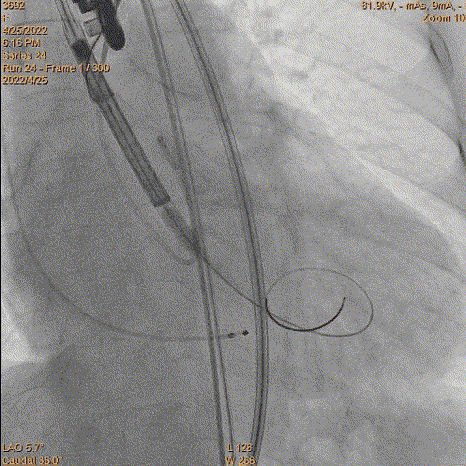

3、球囊预扩:由于钙化严重球囊无法通过,遂使用圈套器抓捕球囊。

套圈器抓球囊过瓣

20mm球囊预扩

导丝位置改变

对侧上圈套器准备

4、跨瓣:瓣膜跨瓣出现困难,计划使用圈套器。由于没有22F大鞘,内连鞘无法拆卸,选择左侧穿刺导入导管。右侧双导丝,送入Lunderquist,心室较大。扩张后,血压较稳定。经尝试无法退球囊,撤出系统。通过对侧使用抓捕器,将导丝全撤,导入AL1.0导管重新跨瓣。鉴于左侧入路有角度,使用泥鳅导丝带上导管,做圈套器。顺利抓住J型导丝,抓捕器顺利抓捕瓣膜过瓣。